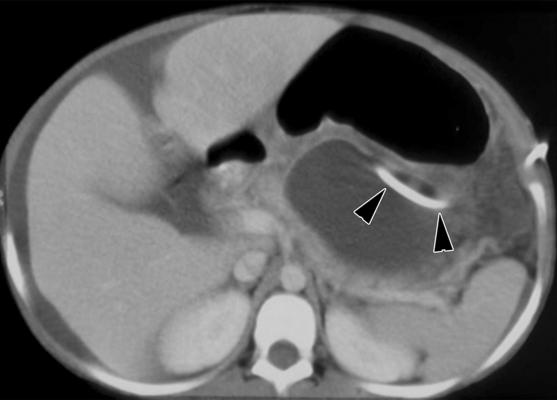

Assessing emergency department visits from 1996 to 2007, researchers found an increase of CT use from 3.2 percent of patient visits to 13.9 percent. Rates of growth were highest for abdominal pain, flank pain, chest pain and shortness of breath, all of which can be symptoms of life-threatening emergencies.

CT scans are powerful and provide a lot of information quickly that can be especially useful in the emergency department, where patients are often very sick and time is critical. CT scans allow doctors to arrive at a diagnosis quickly.